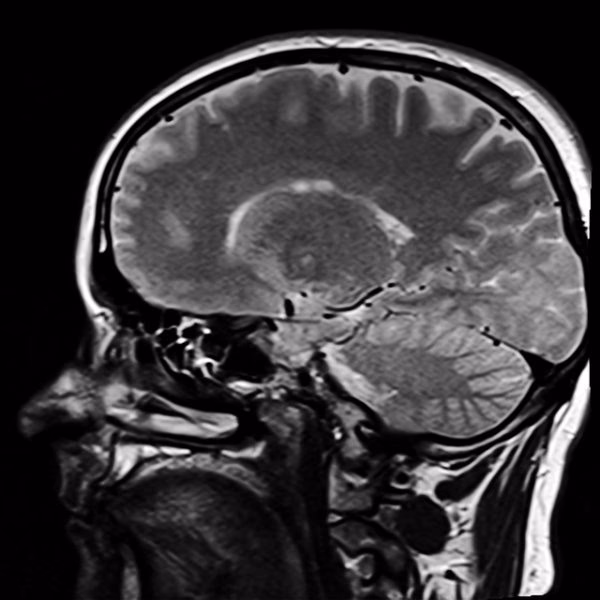

Para entender los riesgos, primero debemos comprender cómo funciona una máquina de resonancia magnética. Su corazón es un imán superconductor extremadamente potente. ¿Qué tan potente? Los campos magnéticos que genera pueden ser hasta 25,000 veces más fuertes que el campo magnético de la Tierra. Esta fuerza es la que permite alinear los protones de agua en nuestro cuerpo para luego, mediante ondas de radio, generar imágenes detalladas de nuestros órganos, tejidos y huesos.